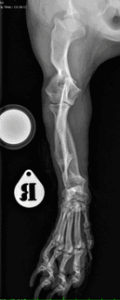

If your pet’s front leg looks “crooked,” “bowed,” or the paw points outward/inward, your pet may have Angular Limb Deformity (ALD)—most commonly affecting the radius and ulna (the two forearm bones) (see Figure 1).

ALD is a condition where a growing bone—most often the radius in the forelimb—develops an abnormal curve, angle, or twist. The good news: with careful planning and modern orthopedic techniques, your pet can usually be safely and accurately treated—and return to an active, comfortable life. This article focuses on front limbs; however, the principles of diagnosis and treatment often apply to both front and back limbs.

X‑rays (radiographs): Two standard views are typical, though more views may be taken per limb to measure where and how much the limb is bowed or angled (Figure 2).